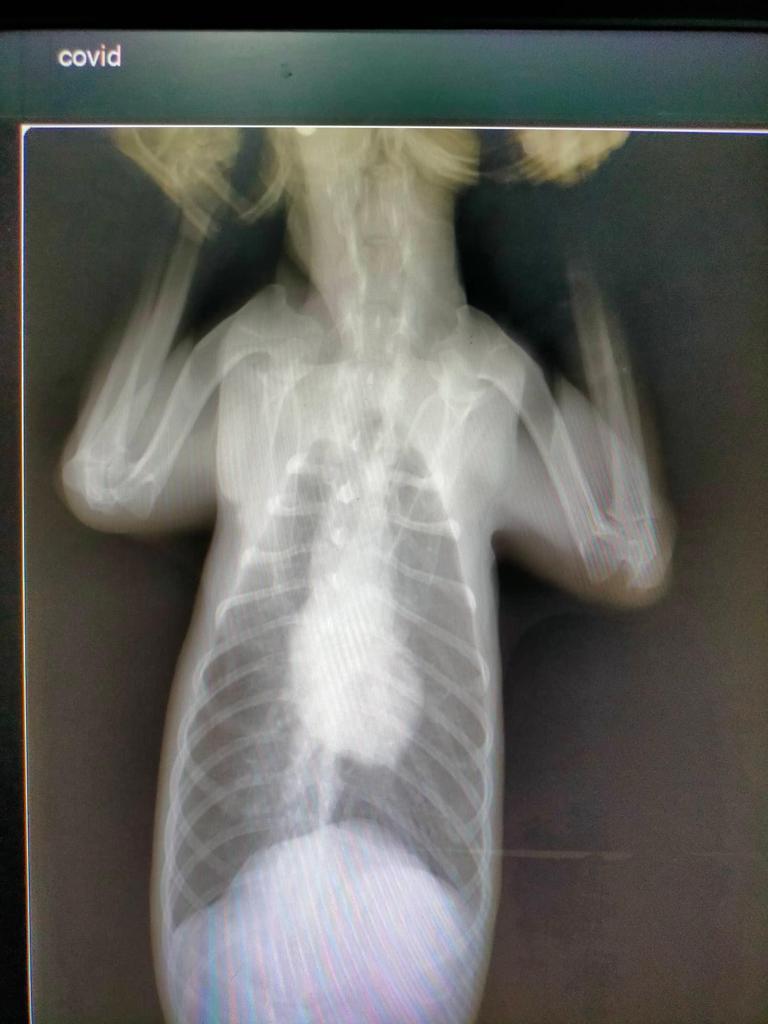

There is no doubt that the tumor needs to be removed. Although Kai was tested negative for distemper, he is positive for ehrlichia. He has high infection, anemia, and a moderately low platelet count. He has possible pancreatitis and is very very stressed - probably also due to severe tumor. He also has an infection of his burdened liver.

Most of these things are caused by the very existence of the tumor, hence the need for very urgent and expensive surgery. Of course complications may arise, we cannot rule this out... But the tumor will only grow bigger and more painful.

Kai suffers from pulmonary opacification. This condition needs to be treated firstly, before he can undergo the surgery. These costs cannot be afforded by owners as well.